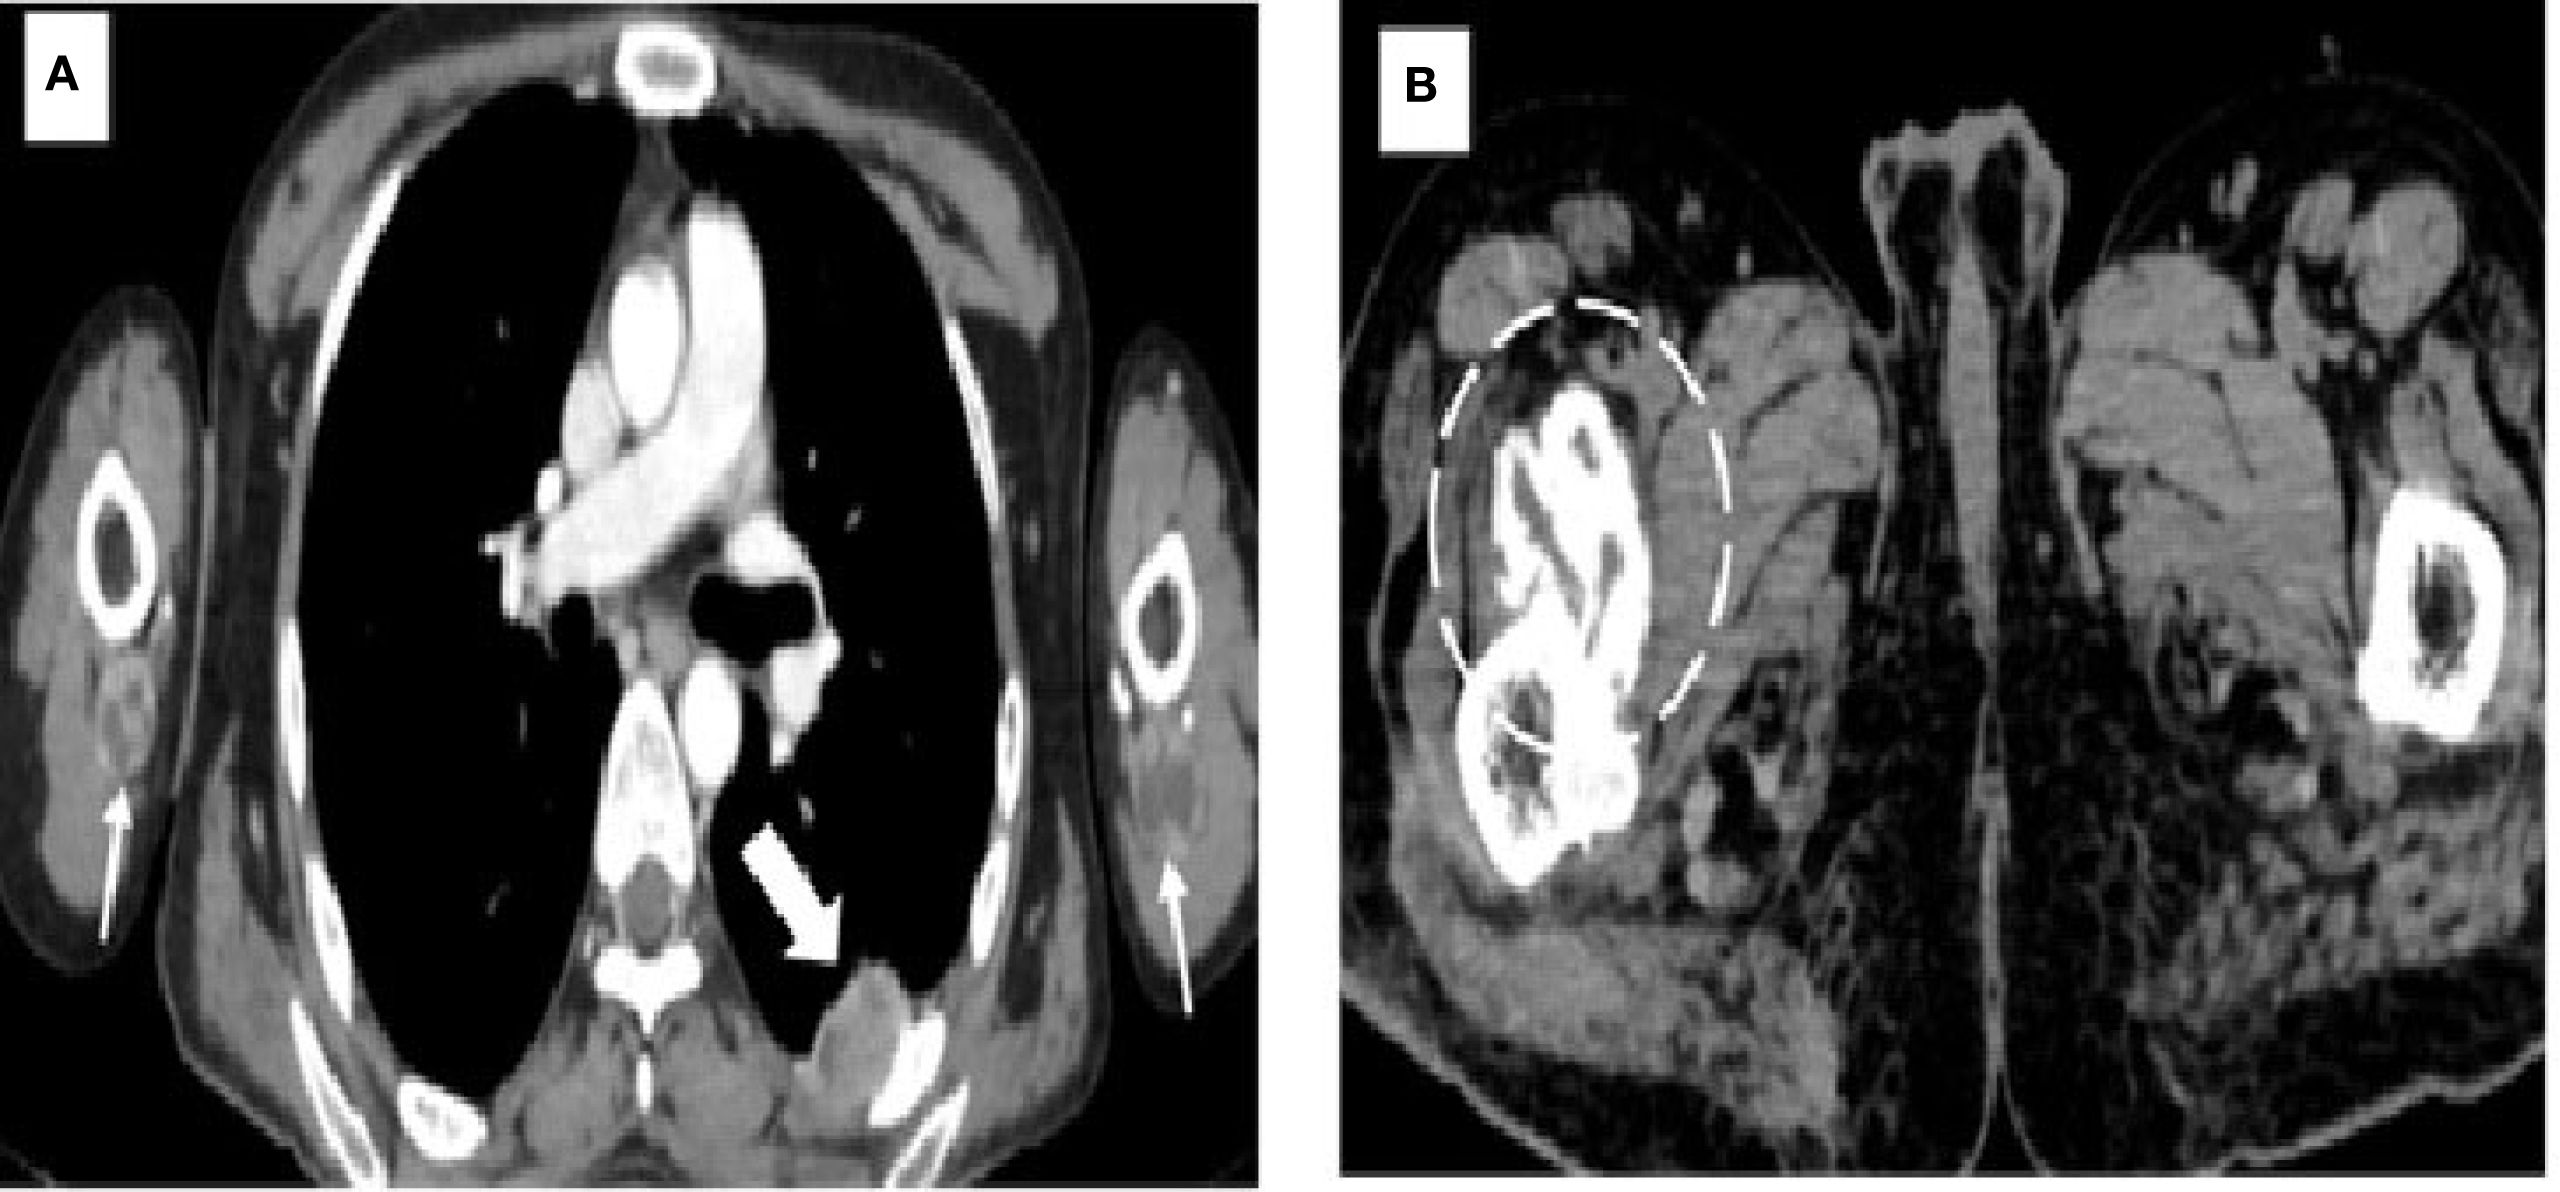

The patient initially underwent an ultrasound of the abdomen and other symptomatic regions, which revealed multiple (from four to five) well-defined, thick-walled cystic lesions in the pelvis (Figure 1A), the largest along the iliac bone measuring 5.3 cm × 6.5 cm × 7 cm [anteroposterior (AP) × transverse diameter (TD) × craniocaudal (CC)]. These cysts showed daughter cysts in a spoke-wheel pattern and hydatid sand, consistent with CE2 active-stage hydatid disease. Additional cystic lesions were identified in the suprasternal region, the anterior chest wall, the extensor compartments of both arms, and the right thigh. A contrast-enhanced computed tomography (CECT) confirmed these findings, demonstrating internal septations, daughter cysts, and septal calcifications in the pelvic cavity (Figures 1B, C), infraclavicular regions, pleura, and extremities (Figures 2A, B). Intraosseous cysts were also seen in the ramus and angle of the right mandible, measuring 3.4 cm × 4 cm × 3.4 cm (AP × TD × CC) (Figures 1E, F), showing a calcified rim without daughter cysts, corresponding to CE5 inactive cysts. CT additionally revealed multiple cysts at the craniovertebral junction, the cervical spine, and the dorsal spine, all showing peripheral rim enhancement, but no pericystic inflammation.

Figure 2. Images demonstrating hydatid cysts in the thorax, upper limbs, and pelvis. (A) Axial contrast-enhanced CT of the thorax showing a pleural hydatid cyst (solid white arrow) located posteriorly, with characteristic rim and septal enhancement. Additional hydatid cysts are seen in the extensor compartments of both arms (white arrows), situated beneath the triceps muscles. (B) Axial CT image of the pelvis revealing a well-circumscribed cystic lesion with calcified margins (dashed circle) and no internal daughter cysts, consistent with an inactive hydatid cyst (WHO type CE5). This lesion is located within the right iliopsoas muscle near its insertion at the lesser trochanter of the femur.